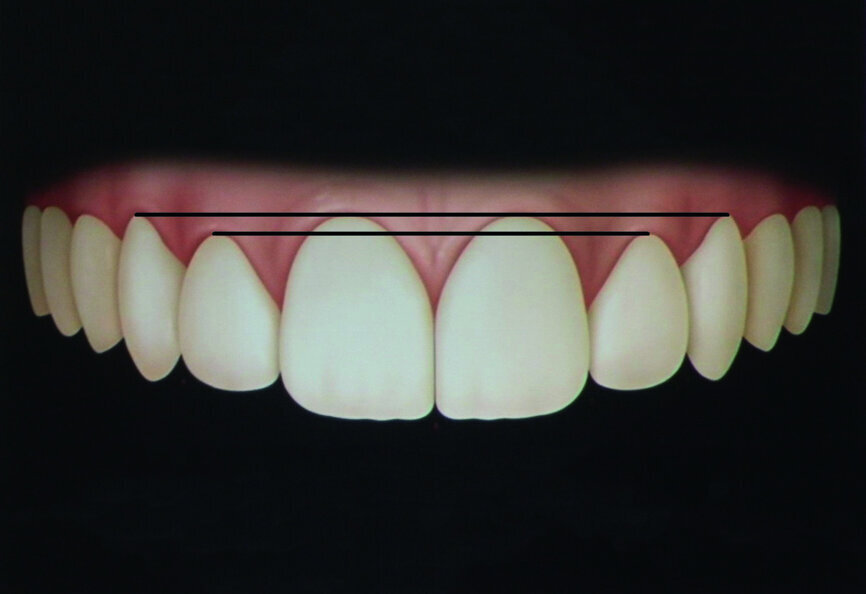

- Gingival height of contour of the upper anterior teeth (Fig. 1): central incisors and canines are more superior than that of the lateral incisors.

- The long axis of the central incisor and the canines should be slightly mesial to the gingival height of contour (Fig. 2).

- The long axis of the upper lateral incisor should be coincidental to the gingival height of contour (Fig. 2).

- Dental proportions: the width of wellproportioned teeth should be approximately 60 % to 75 % of their height (Fig. 3).